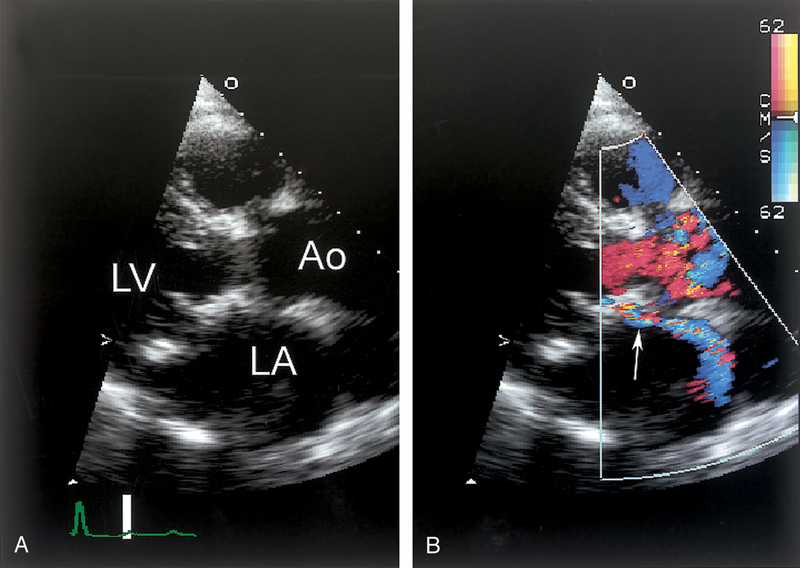

فحوصات تشخيصية لبعض امراض القلب والشرايين التاجية